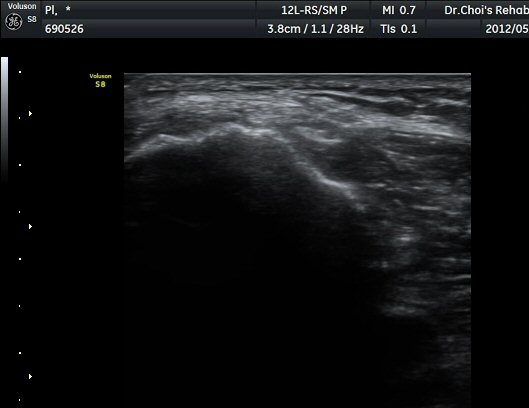

ŽÃËÀÚ¸¦ ¾Æ·¡·Î À̵¿ÇÏ¿© ºñ°ñµÎ ºÎÀ§±îÁö ÃѺñ°ñ½Å°æÀÇ ÁÖÇàÀ» µû¶ó ½Å°æÀ» È®ÀÎÇÏ¿´´Ù(±×¸² 3, 4).

ŽÃËÁö¸¦ Á¶±Ý ´õ ¾Æ·¡·Î À̵¿ÇÏ´Ï »ÀÀÇ µÎ²²°¡ °¨¼ÒÇÏ´Â °ÍÀ» º¸°í ºñ°ñÀÇ ¸ñ ºÎÀ§¸¦ °üÂûÇϰí ÀÖÀ½À» ¾Ë ¼ö ÀÖ°í ÃѺñ°ñ ½Å°æÀº ºñ°ñ ¸ñ Ç¥Ãþ¿¡¼­ °üÂûµÈ´Ù(±×¸² 5).